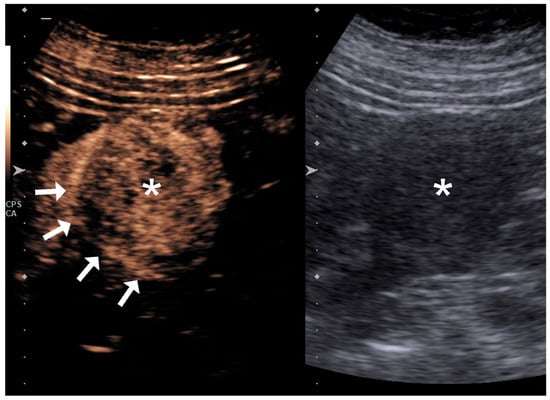

4.1. Qualitative Evaluation